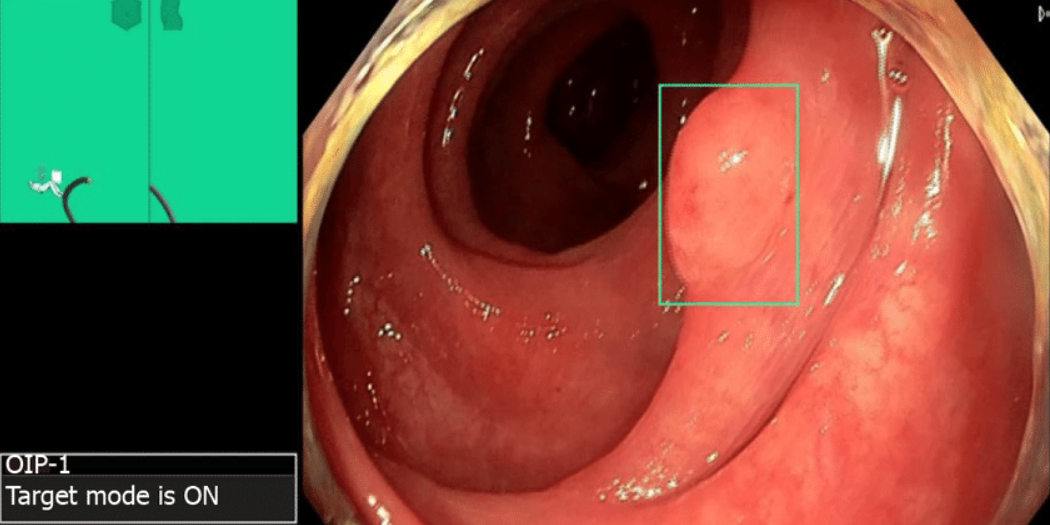

Искусственный интеллект в эндоскопии - это программно-аппаратные комплексы, которые анализируют изображение с эндоскопа в реальном времени и выделяют участки, наиболее соответствующие патологии.

В отличие от человека, который может устать или элементарно отвлечься, алгоритм сохраняет постоянную концентрацию на каждом кадре.

🔹 CADe (Computer-Aided Detection) - системы программного обнаружения. Их задача - находить подозрительные участки слизистой. Чаще всего речь идет о полипах толстой кишки. Алгоритм выделяет их цветным маркером на экране, акцентируя внимание врача. CADe работает как сканер, постоянно прочесывающий поле зрения.